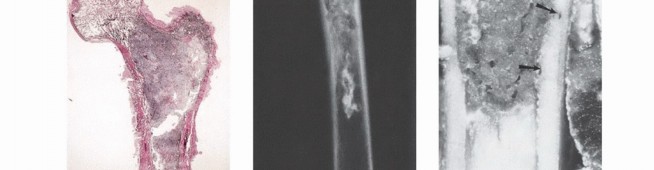

Tumor Growth Dynamics and the Pseudocapsule

Unlike carcinomas, which grow via direct infiltrative destruction, sarcomas typically form a solid, cohesive mass that expands centrifugally. The periphery of the lesion is the most biologically active and least mature zone.

Benign lesions are often constrained by a true capsule composed of compressed, mature normal cells. In stark contrast, sarcomas are enveloped by a "pseudocapsule." This reactive zone consists of compressed malignant cells, a fibrovascular stroma, and a dense inflammatory infiltrate interacting with the surrounding host tissue. The pseudocapsule is highly deceptive; it is not a true anatomic barrier but rather a tumor-host interface.

The thickness and integrity of this reactive zone vary with tumor grade. High-grade sarcomas feature a poorly defined, highly permeable reactive zone that is frequently invaded by microscopic tumor extensions.

* Satellite Lesions: Microscopic or macroscopic tumor foci located within the reactive zone/pseudocapsule.

* Skip Metastases: Tumor nodules that have broken through the pseudocapsule and reside outside the reactive zone but remain within the same anatomic compartment. These represent locoregional micrometastases that have spread via local tissue planes or marrow sinusoids, independent of systemic circulation. The presence of skip metastases (seen in <5% of osteosarcomas preoperatively) is a dire prognostic sign and accounts for local recurrences when seemingly adequate margins are achieved without recognizing the skip lesion. Low-grade sarcomas may interdigitate into the reactive zone but rarely form true skip metastases.

- Plain Radiography: The cornerstone of initial evaluation. It accurately predicts the diagnosis in over 80% of extremity bone tumors. It defines the lesion's location, zone of transition (narrow/sclerotic = benign/slow; wide/permeative = malignant/aggressive), cortical destruction, and periosteal reactions (Codman triangle, onion-skinning, sunburst pattern).

- Magnetic Resonance Imaging (MRI): The gold standard for evaluating the local extent of the tumor. It accurately defines the intramedullary extent (allowing calculation of bone resection levels), soft tissue extension, joint involvement, and the presence of skip metastases. T1-weighted images best define marrow replacement; T2-weighted and STIR sequences highlight peritumoral edema and the soft tissue mass. Contrast enhancement differentiates cystic from solid components and clarifies neurovascular proximity.